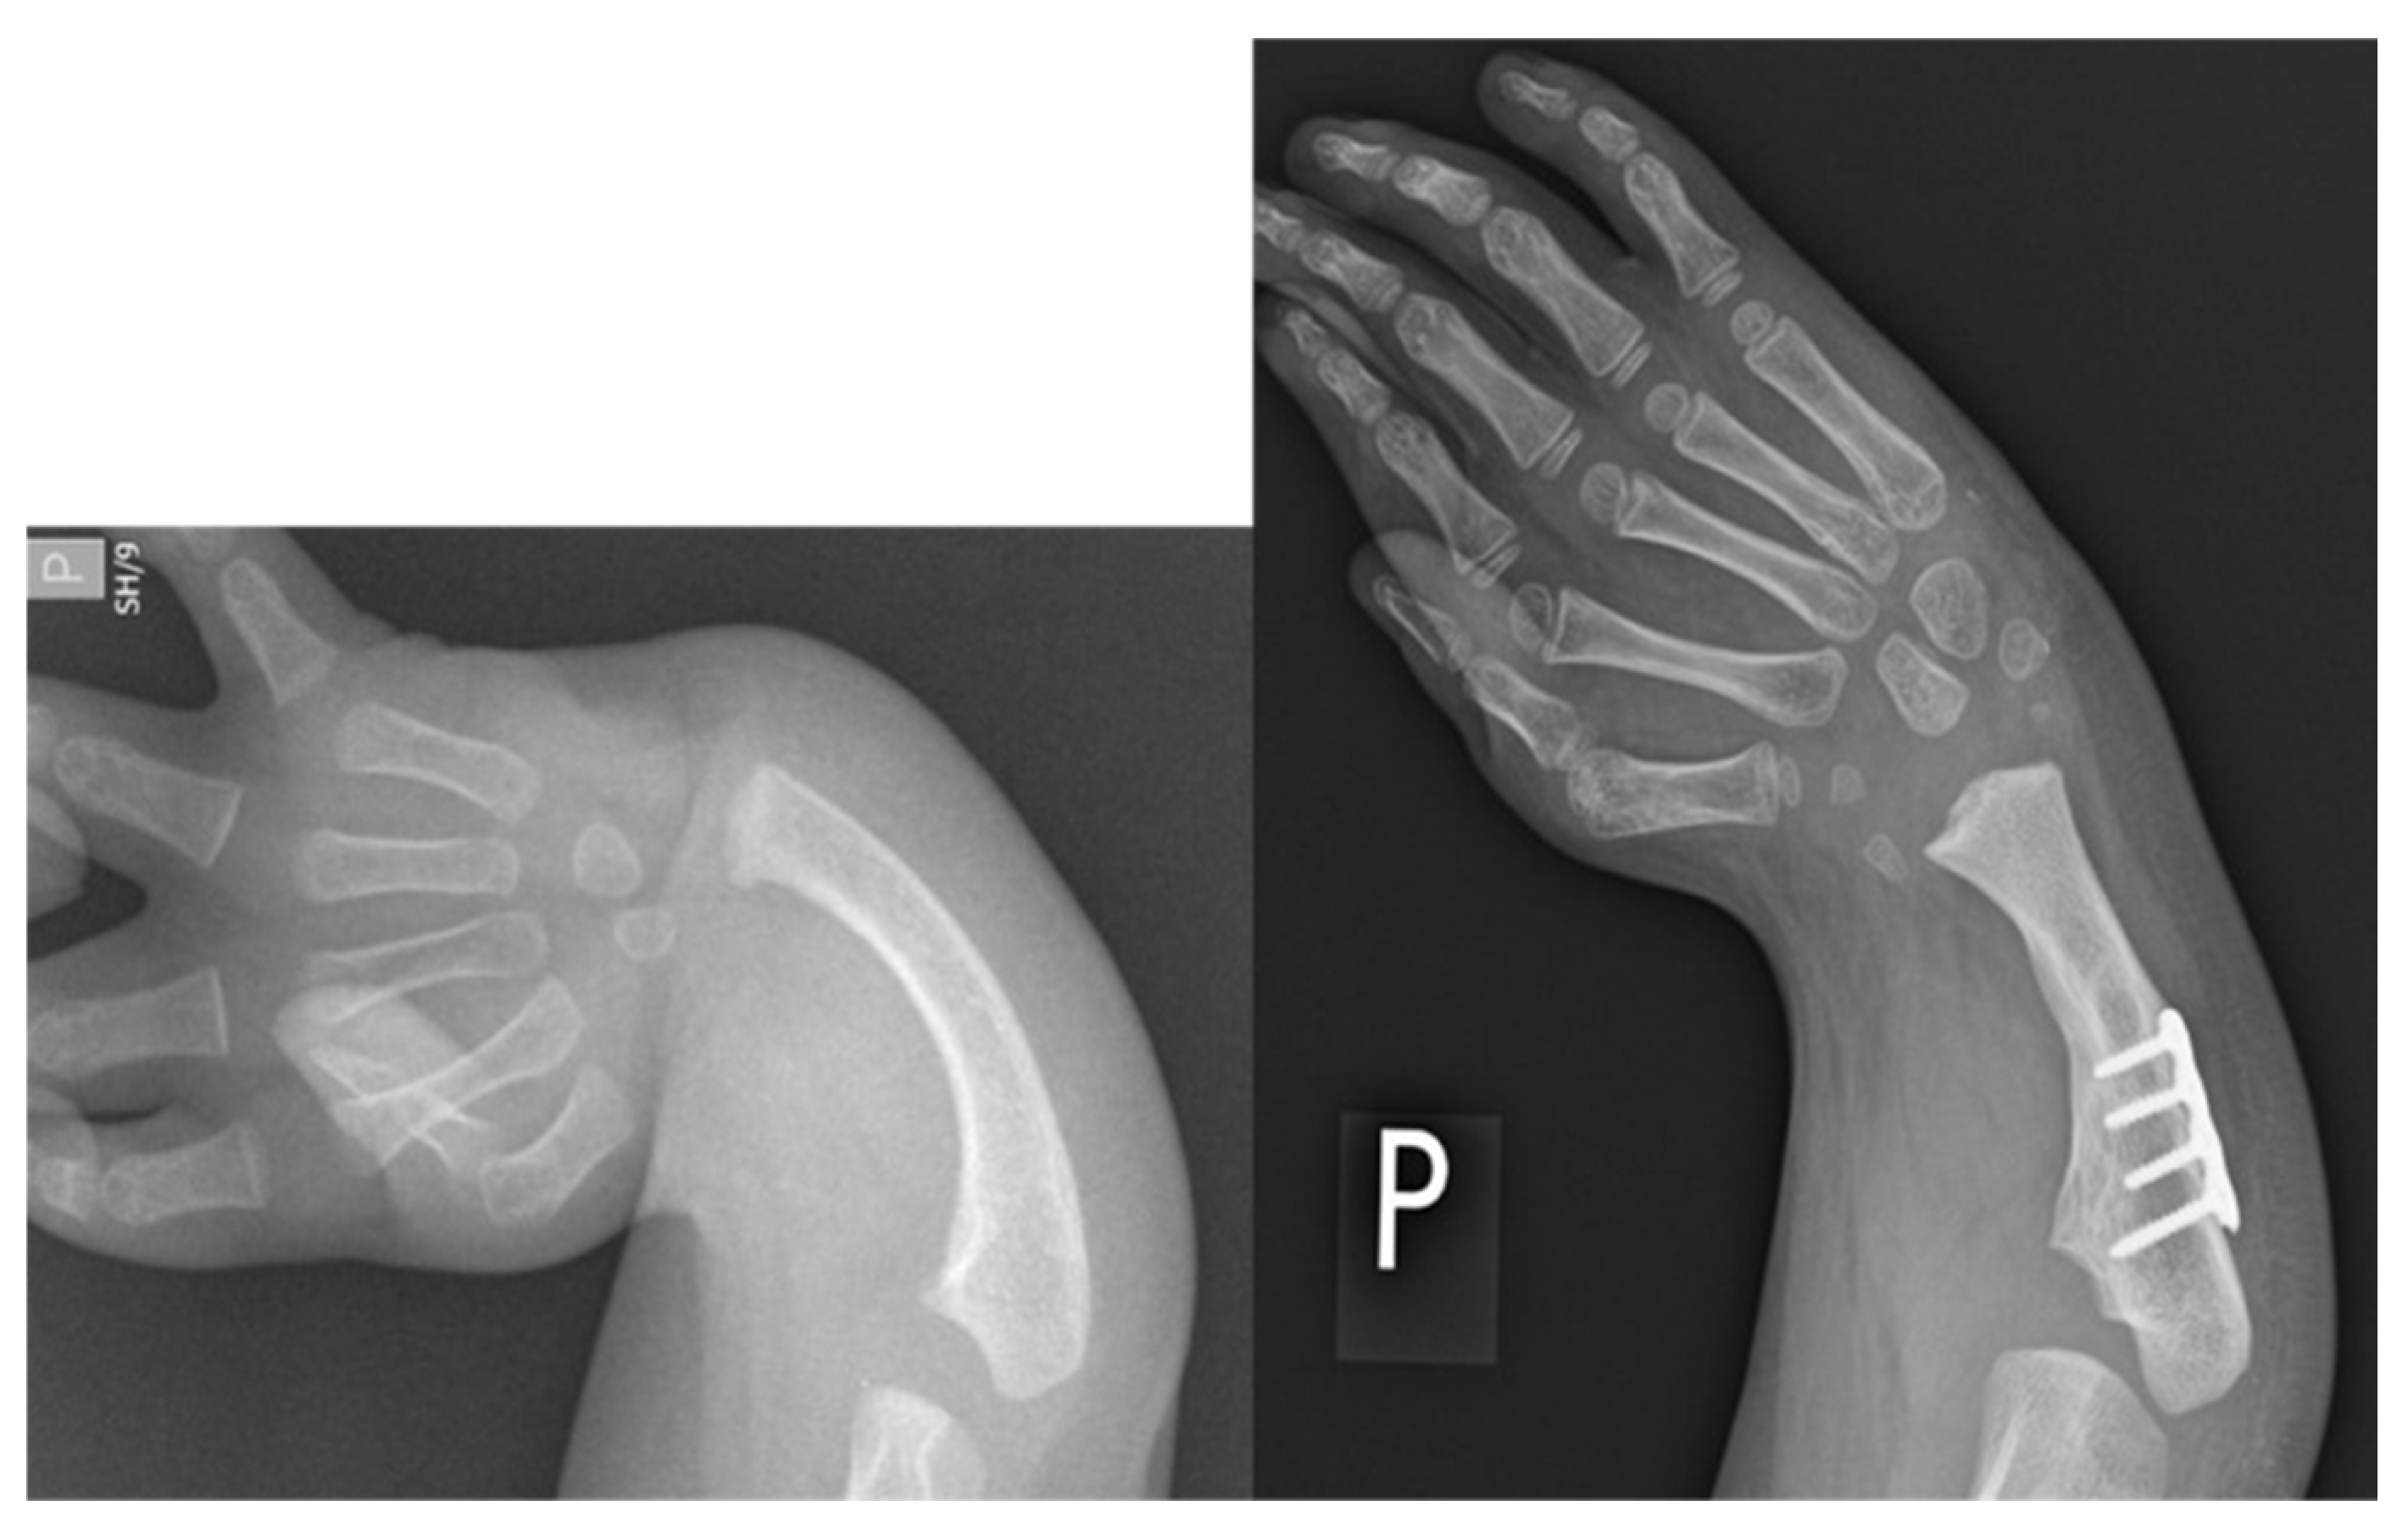

Figure 5.

Case 6 preop radiographs (left); postop radiograph after ulnarization G3 (right). Note the hypertrophy of the head of the ulna after surgery.